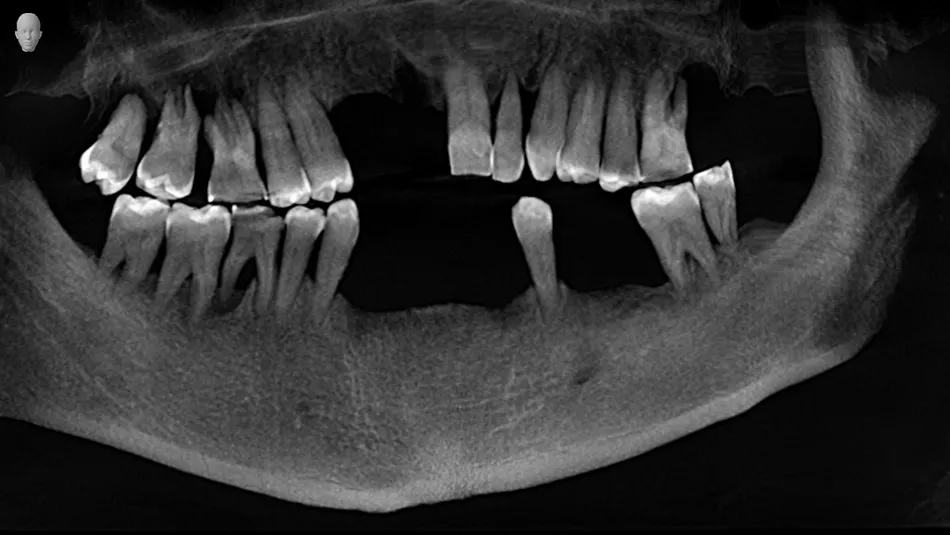

22. Post operative radiographs of the implants and with restorations screwed in place.

22